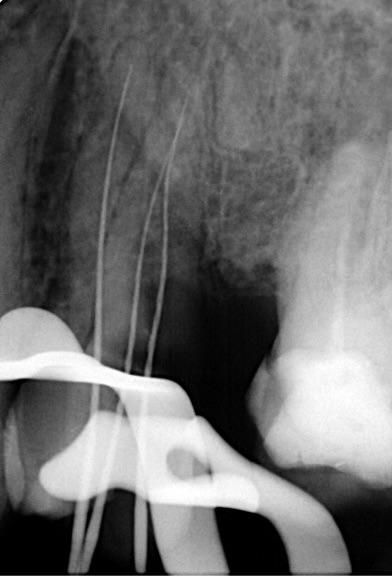

- Safely negotiating and managing a highly intricate, molar-like canal network within the inherently more restricted anatomical dimensions of a premolar root.

- Performing conservative shaping that respected the original canal trajectories and internal morphology without unnecessary sacrifice of dentin, particularly in the pericervical region.

Adequate access was essential—not only to locate and negotiate the canal system but also to do so while conserving as much tooth structure as possible. Once the decay was fully removed and access achieved, shaping was carried out using the DENCO Chameleon Dual Shaper. This instrument allowed for conservative and controlled preparation, effectively preserving the original canal anatomy and minimizing excessive dentin removal. Respecting the internal morphology throughout the procedure was key to maintaining canal integrity.